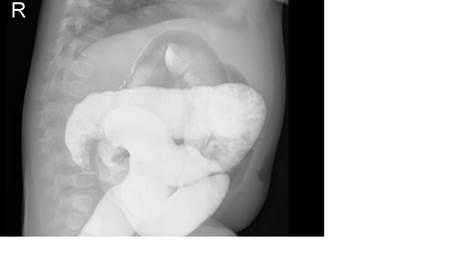

На рисунках 4 и 5 представлена картина кишечной инвагинации при рентгенологическом исследовании.

Рис. 4. Ирригограмма при тугом наполнении взвесью сульфата бария - симптом «клешней рака»